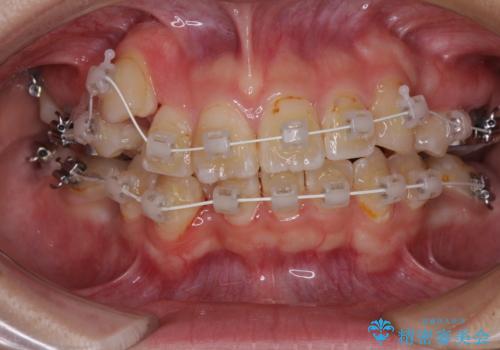

- 審美装置

- 4年4ヶ月

- 30回以上

重度叢生のため、大臼歯をしっかりと咬合させるために、下顎は左右第二小臼歯を、上顎は前歯部の叢生を解消するために左右第一小臼歯を抜歯し、口元の突出感を改善するために、上顎大臼歯が前方に移動しないようにするために、補助装置による架強固定を行うこととしました。

叢生は思ったよりも早期に改善されましたが、舌の突出癖による上下前歯の非接触が全く改善されず、2年間ほど治療期間が延びる結果となってしまいました。